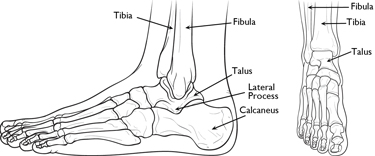

AnatomyThe talus is the bone that makes up the lower part of the ankle joint (the tibia and fibula bones of the lower leg make up the upper part of the ankle joint). The talus sits above the heel bone (calcaneus). Together, the talus and calcaneus form the subtalar joint, which is important for walking, especially on uneven ground.

The talus is the main connector between the foot and leg, helping to transfer weight and pressure forces across the ankle joint. It is largely covered by articular cartilage, the white slippery material that covers all joint surfaces. This cartilage allows the talus to move smoothly against its neighbor bones.

Fractures occur in all parts of the talus bone. Most commonly, the talus breaks in its mid-portion, called the "neck." The neck is between the "body" of the talus, located under the tibia, and the "head," located further down the foot.

Another common site for talus fractures is along the outside of the bone where it juts out slightly. This area of the bone is called the "lateral process." Fractures of the lateral process often occur when the ankle is forced out to the side and are commonly seen in snowboarders.

The talus bone sits between the bones of the lower leg and the calcaneus (heel bone).